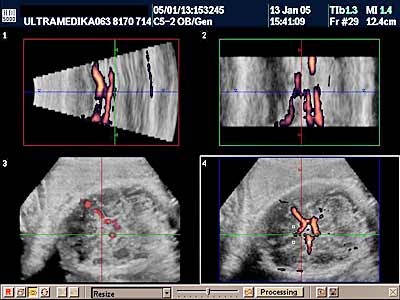

A) Savremena dijagnostika korišćenjem Broad band kolor Dopplera (Broad band-CD) i kolor Power Dopplera (CPD) bez obzira na količinu krvi koja prolazi kroz vaskularnu anomaliju i bez obzira pod kojim uglom je moguće poslati ultrazvučni talas, je u stanju da postavi dijagnozu ove ozbiljne vaskularne malformacije CNS. U nepovoljnim uslovima standardna ultrazvučna tehnika sa CD nije u stanju da prikaže ni normalne krvne sudove Wilisovog šestougla niti duboke drenažne vene . Jedino savremena ultrazvučna tehnika je u stanju da postavi dijagnozu bez obzira na položaj ploda koji obično bitno ne menja svoju poziciju u toku pregleda u III trimestru trudnoće. Takođe CPD tehnika je u stanju da proceni tačno hemodinamiku moždane i srčane cirkulacije i da tačnu prognozu. Ovo je važno jer se neke aneurizme vene Galen-i mogu lečiti nakon rađanja deteta embolizacijom krvnih sudova.

B) 3D Sono CT (trodimenzionalna) tehnika, dovodi do kvalitativnog pomaka u odnosu na prethodne godine. Naime 3D Sono CT (trodimenzionalna) tehnika nam omogućava dobijanje kompletnog volumenom mozga. Ako želimo da prikažemo u tri dimenzije krvne sudove koristimo 3D CPA tehniku. Ova tehnika je jako složena, zahteva dodatno vreme, izuzetno poznavanje anatomije i sonomorfološke ultrazvučne anatomije organa i organskih sistema, i sagledavanje promene u sve tri ravne, istovremeno. Da bi smo rendereisali - skupili sve informacije prosečno za to nam je potrebno oko 10 sekundi. Međutim, naknadnim multiplanarnim prikazivanjem i detaljnom analizom velikog broja dobijenih ultrazvučnih slika odgovarajućih preseka kompletne moždane cirkulacije potrebno nam je najmanje 10-15 minuta.

Do sada u svetskoj literaturi je publikovano postavljanje tačne dijagnoze sa sagledavanjem svih aspekata ove anomalije jedinio korišćenjem 3D Sono CT tehnike uz pomoć kompjuterskog alata kao što je SPIN i DOT. Ova 3D Sono CT tehnika u dijagnozi aneurizme vene Galen-i nam omogućava sledeće: